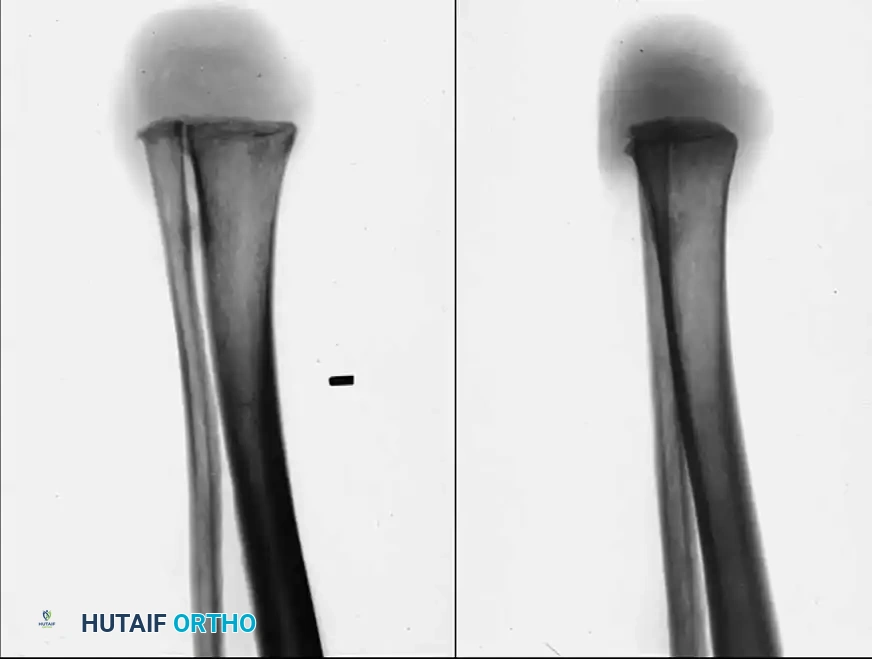

The chief objection to the classic Syme amputation is cosmetic. Because the distal tibial metaphysis flares outward and is covered by thick, heavy plantar skin, the resulting stump is inherently large and bulbous. Consequently, the prosthesis required to accommodate this stump is often bulky, which is why this amputation has historically been less recommended for female patients seeking a highly cosmetic result.

To address the cosmetic shortcomings of the classic technique, Sarmiento described a modification that produces a less bulbous, more cylindrical stump.

* Technique: The tibia and fibula are transected approximately 1.3 cm proximal to the ankle joint, and the medial and lateral malleoli are completely excised.

* Advantage: This produces a stump only slightly larger in circumference than the diaphyseal portion of the leg. It allows the patient to be fitted with a prosthesis incorporating an expandable socket rather than a bulky removable window, vastly improving cosmesis.